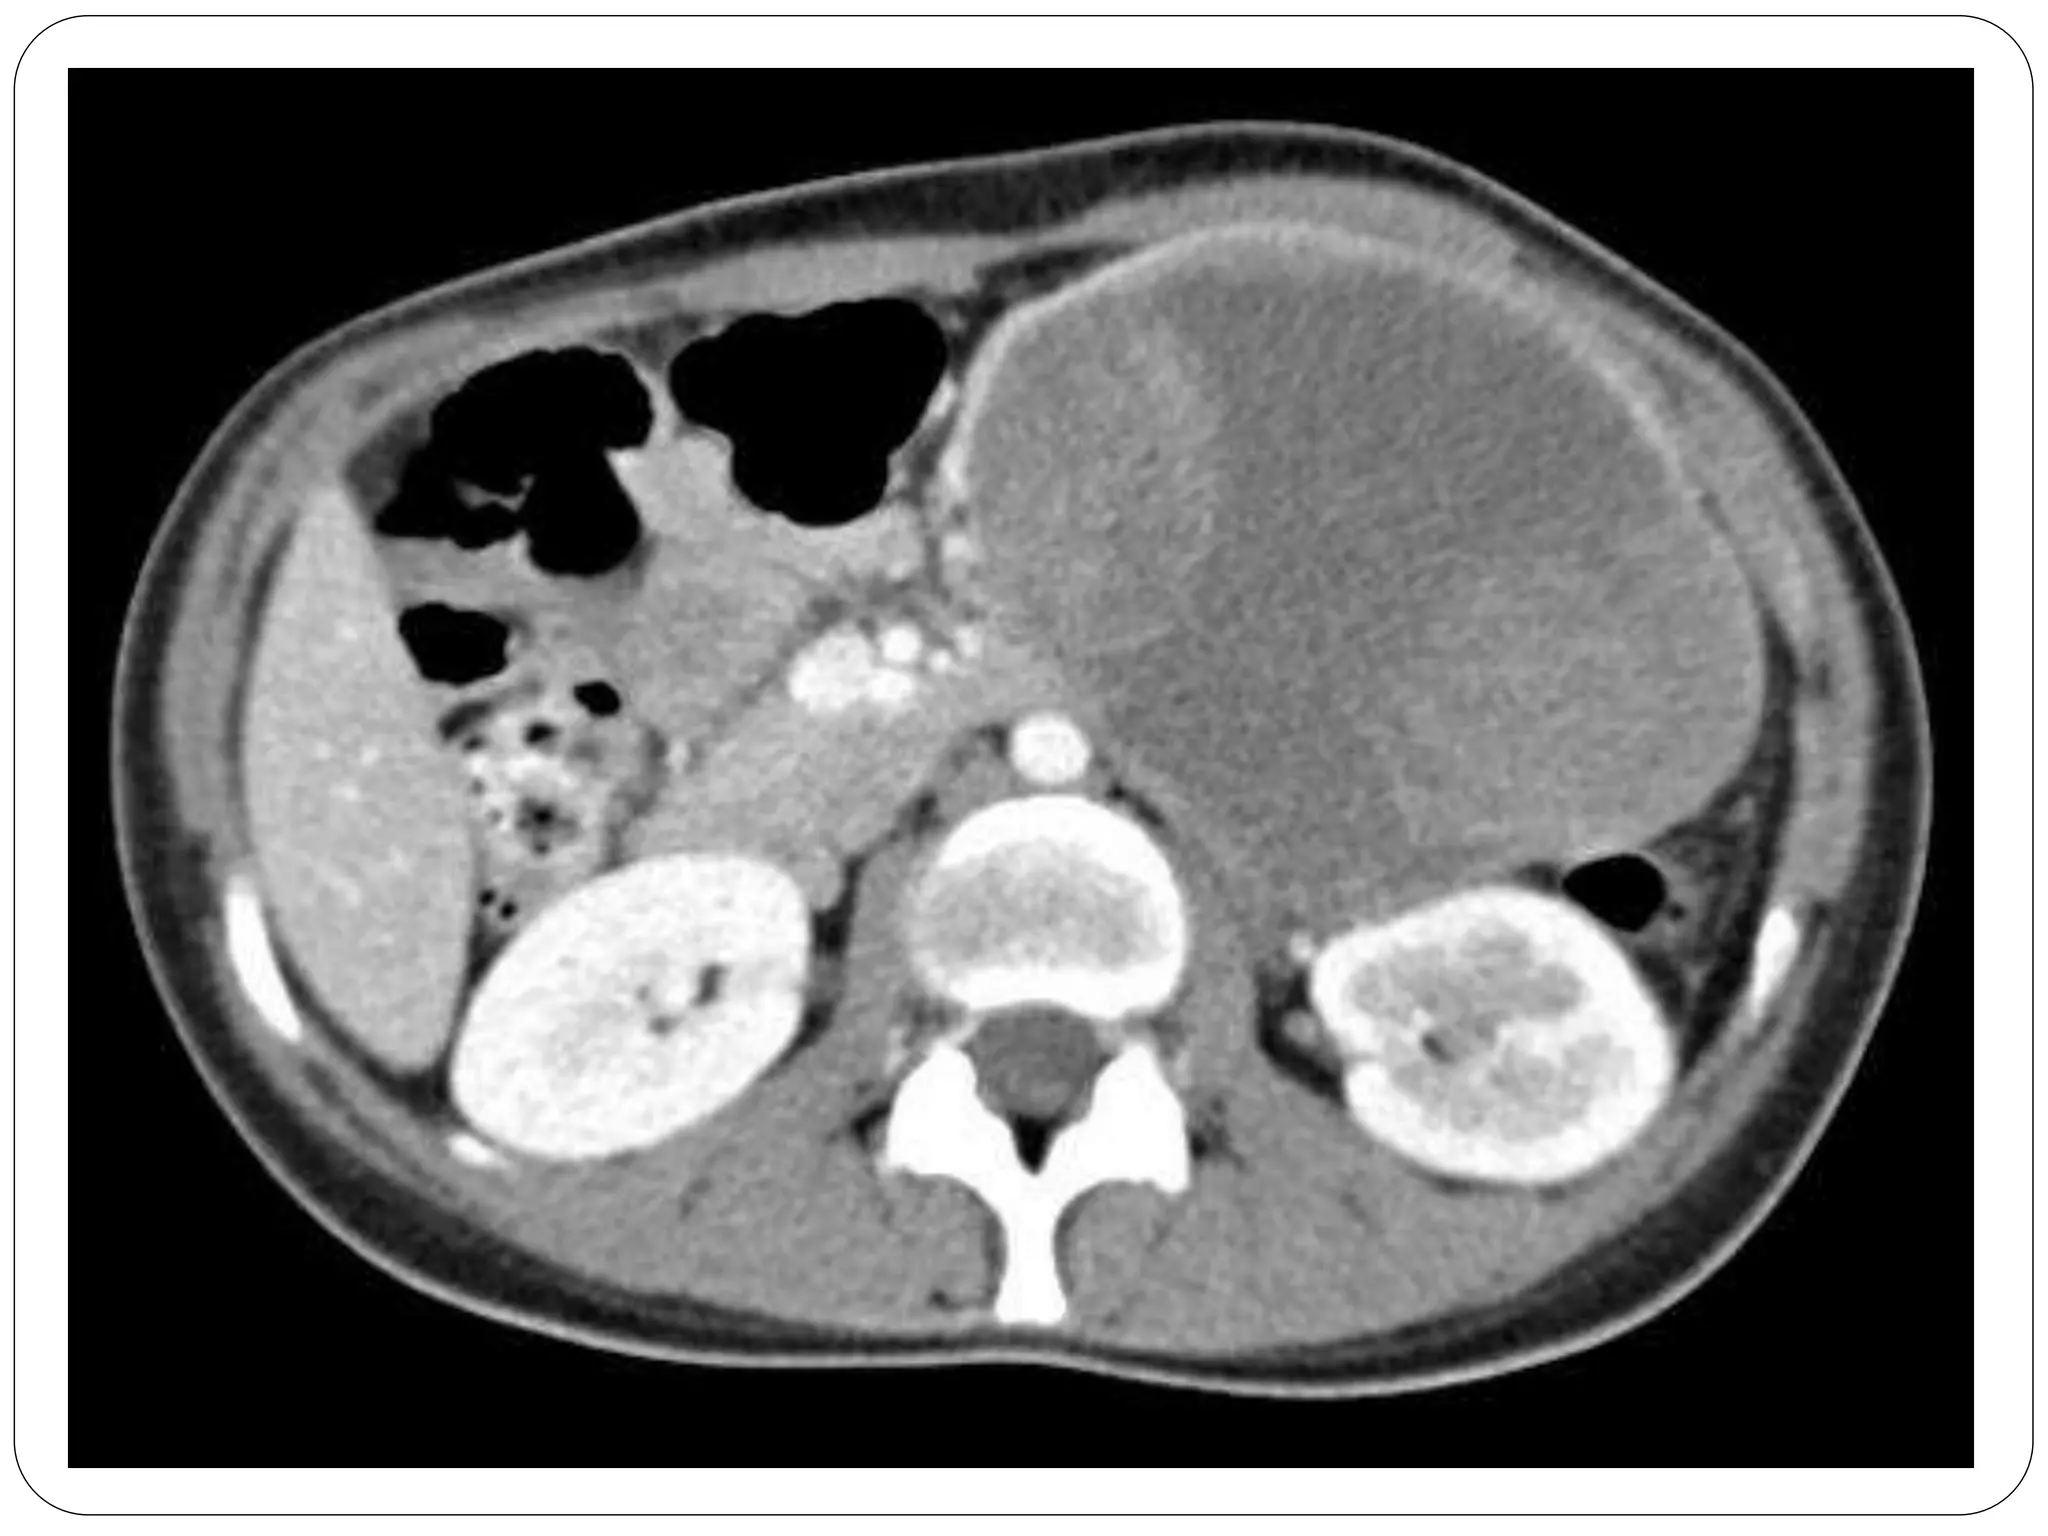

• #5 Well-circumscribed neoplasm with solid and cystic components Calcifications in ~ 30%

• #6 Well-circumscribed neoplasm with solid and cystic components Calcifications in ~ 30%